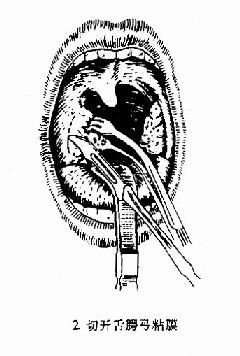

(1)切口:用扁桃体钳夹持扁桃体向内、上牵拉,暴露舌腭弓游离缘与扁桃体之间粘膜皱襞,以弯尖刀切开此处粘膜,并向后切开咽腭弓与扁桃体间部分粘膜。

图6-2 扁桃体切除术(剥离法)